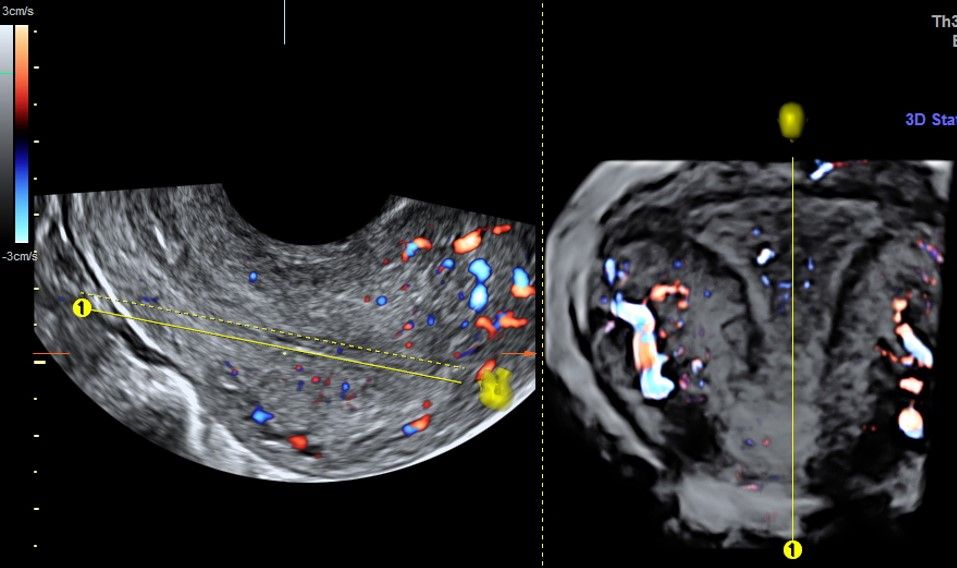

Современные экспертные УЗИ сканеры дают возможность проводить исследования всех органов в 3D. Это позволяет, используя полученный массив данных, получать диагностические сечения в любой плоскости, недоступной для обычного 2D УЗИ. Наиболее интересной является фронтальная. Например, визуализация полости матки. Диагностическая возможность выявления пороков развития превосходит все другие методы (рентгеновские и МРТ). Метод также позволяет уточнить положение ВМК (спирали) в полости матки, расположение миоматозных узлов, расположение плодного яйца на малых сроках, полипов. Сегодня современное экспертное ультразвуковое исследование невозможно без использования 3D УЗИ.